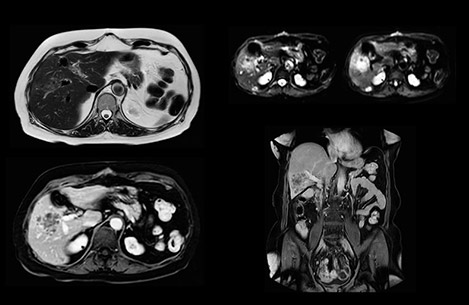

Comparison of liver MRI with and without MultiVane XD motion correction

In this example the image quality of the MultiVane XD images is evidently better than in the images without MultiVane XD. Ingenia 1.5T with dS Torso coil solution.